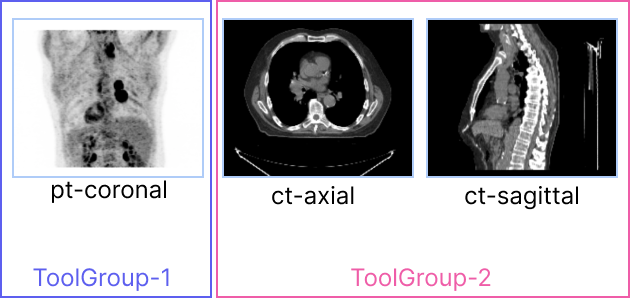

Consider the following set of viewports, and the desired behavior for scrolling and panning.

For ct-axial and ct-sagittal viewports, we want to enable scrolling by mouse wheel and panning by mouse middle button drag.

However, for the pt-coronal which is a Maximum Intensity Projection (MIP) viewport, scrolling through slices

has no meaning, and desired behavior is to rotate the MIP volume by mouse wheel and disable panning.

There is a one-to-one relationship between viewports and tool groups. In other words, no viewport can be part of more than one tool group.